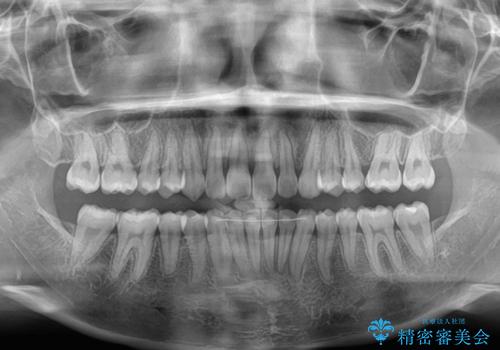

- 上の前歯が前方に飛び出していることを気にして来院された患者様です。

奥歯の咬み合わせをチェックすると、上顎歯列が相対的に前方に位置しているため、補助装置を用いて上顎歯列を確実に後方に移動させ、インビザラインで歯列を整えて行くこととしました。

インビザライン単体でも同様の結果が得られる可能性がありますが、万が一奥歯がうまく後方移動できなかった場合、リカバリーが非常に大変となるため、事前に補助装置を併用して確実に結果が得られるように工夫をしています。